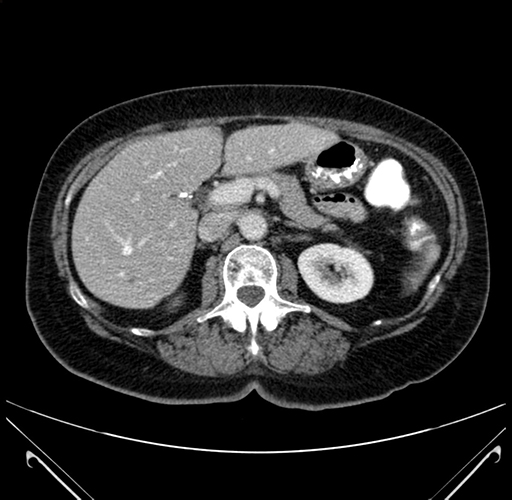

Axial Venous